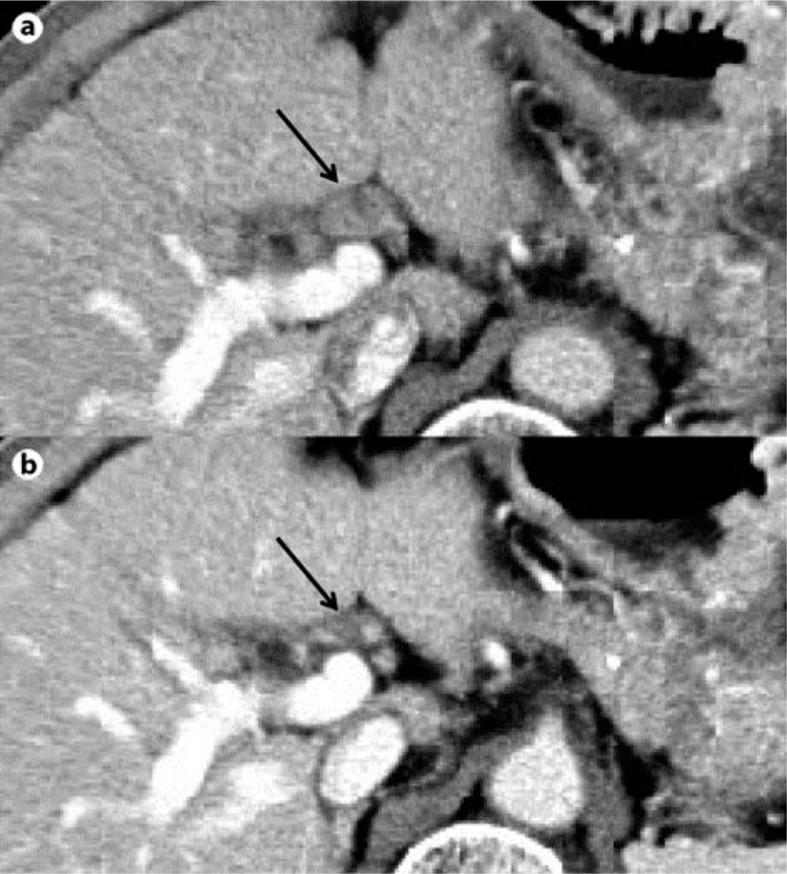

A 60-year-old man received interferon/ribavirin combination therapy for chronic hepatitis C in 2002 and achieved sustained virological response. In 2008, a hepatocellular carcinoma (HCC) with a diameter of 60 mm appeared and surgical resection was performed. In March 2011, the patient was referred to our hospital because of portal lymph node swelling. Abdominal ultrasonography, dynamic CT and dynamic MRI did not show any tumors in the liver, but revealed portal lymph node swelling (18 × 11 mm). Taking the elevation of serum des-γ-carboxy prothrombin and alpha-fetoprotein levels, including the lectin-bound type, into consideration, we made the diagnosis of HCC metastasis to the portal lymph node. We started sorafenib therapy at a dose of 800 mg/day, but discontinued it after 11 days due to grade 3 hand-foot skin reaction and rash. In spite of treatment termination, portal lymph node swelling disappeared and the serum des-γ-carboxy prothrombin and alpha-fetoprotein levels normalized. We considered that our patient achieved complete response to sorafenib according to the Response Evaluation Criteria in Solid Tumors (RECIST). The patient maintains remission up to June 2012, more than 1 year after the discontinuation of sorafenib therapy. Sorafenib could be a good option for unresectable or recurrent HCC.

一名60岁男性于2002年接受干扰素/利巴韦林联合治疗慢性丙型肝炎,并实现了持续病毒学应答。2008年,出现了直径60毫米的肝细胞癌(HCC)并进行了手术切除。2011年3月,该患者因门静脉淋巴结肿大被转诊至我院。腹部超声、动态CT和动态MRI均未显示肝脏有任何肿瘤,但发现门静脉淋巴结肿大(18×11毫米)。考虑到血清去γ-羧基凝血酶原和甲胎蛋白水平升高,包括凝集素结合型,我们诊断为HCC转移至门静脉淋巴结。我们开始使用索拉非尼治疗,剂量为800毫克/天,但由于3级手足皮肤反应和皮疹,在11天后停药。尽管治疗终止,但门静脉淋巴结肿大消失,血清去γ-羧基凝血酶原和甲胎蛋白水平恢复正常。根据实体瘤疗效评价标准(RECIST),我们认为该患者对索拉非尼实现了完全缓解。该患者在索拉非尼治疗停药后1年多,直至2012年6月一直保持缓解状态。索拉非尼可能是不可切除或复发性HCC的一个良好选择。